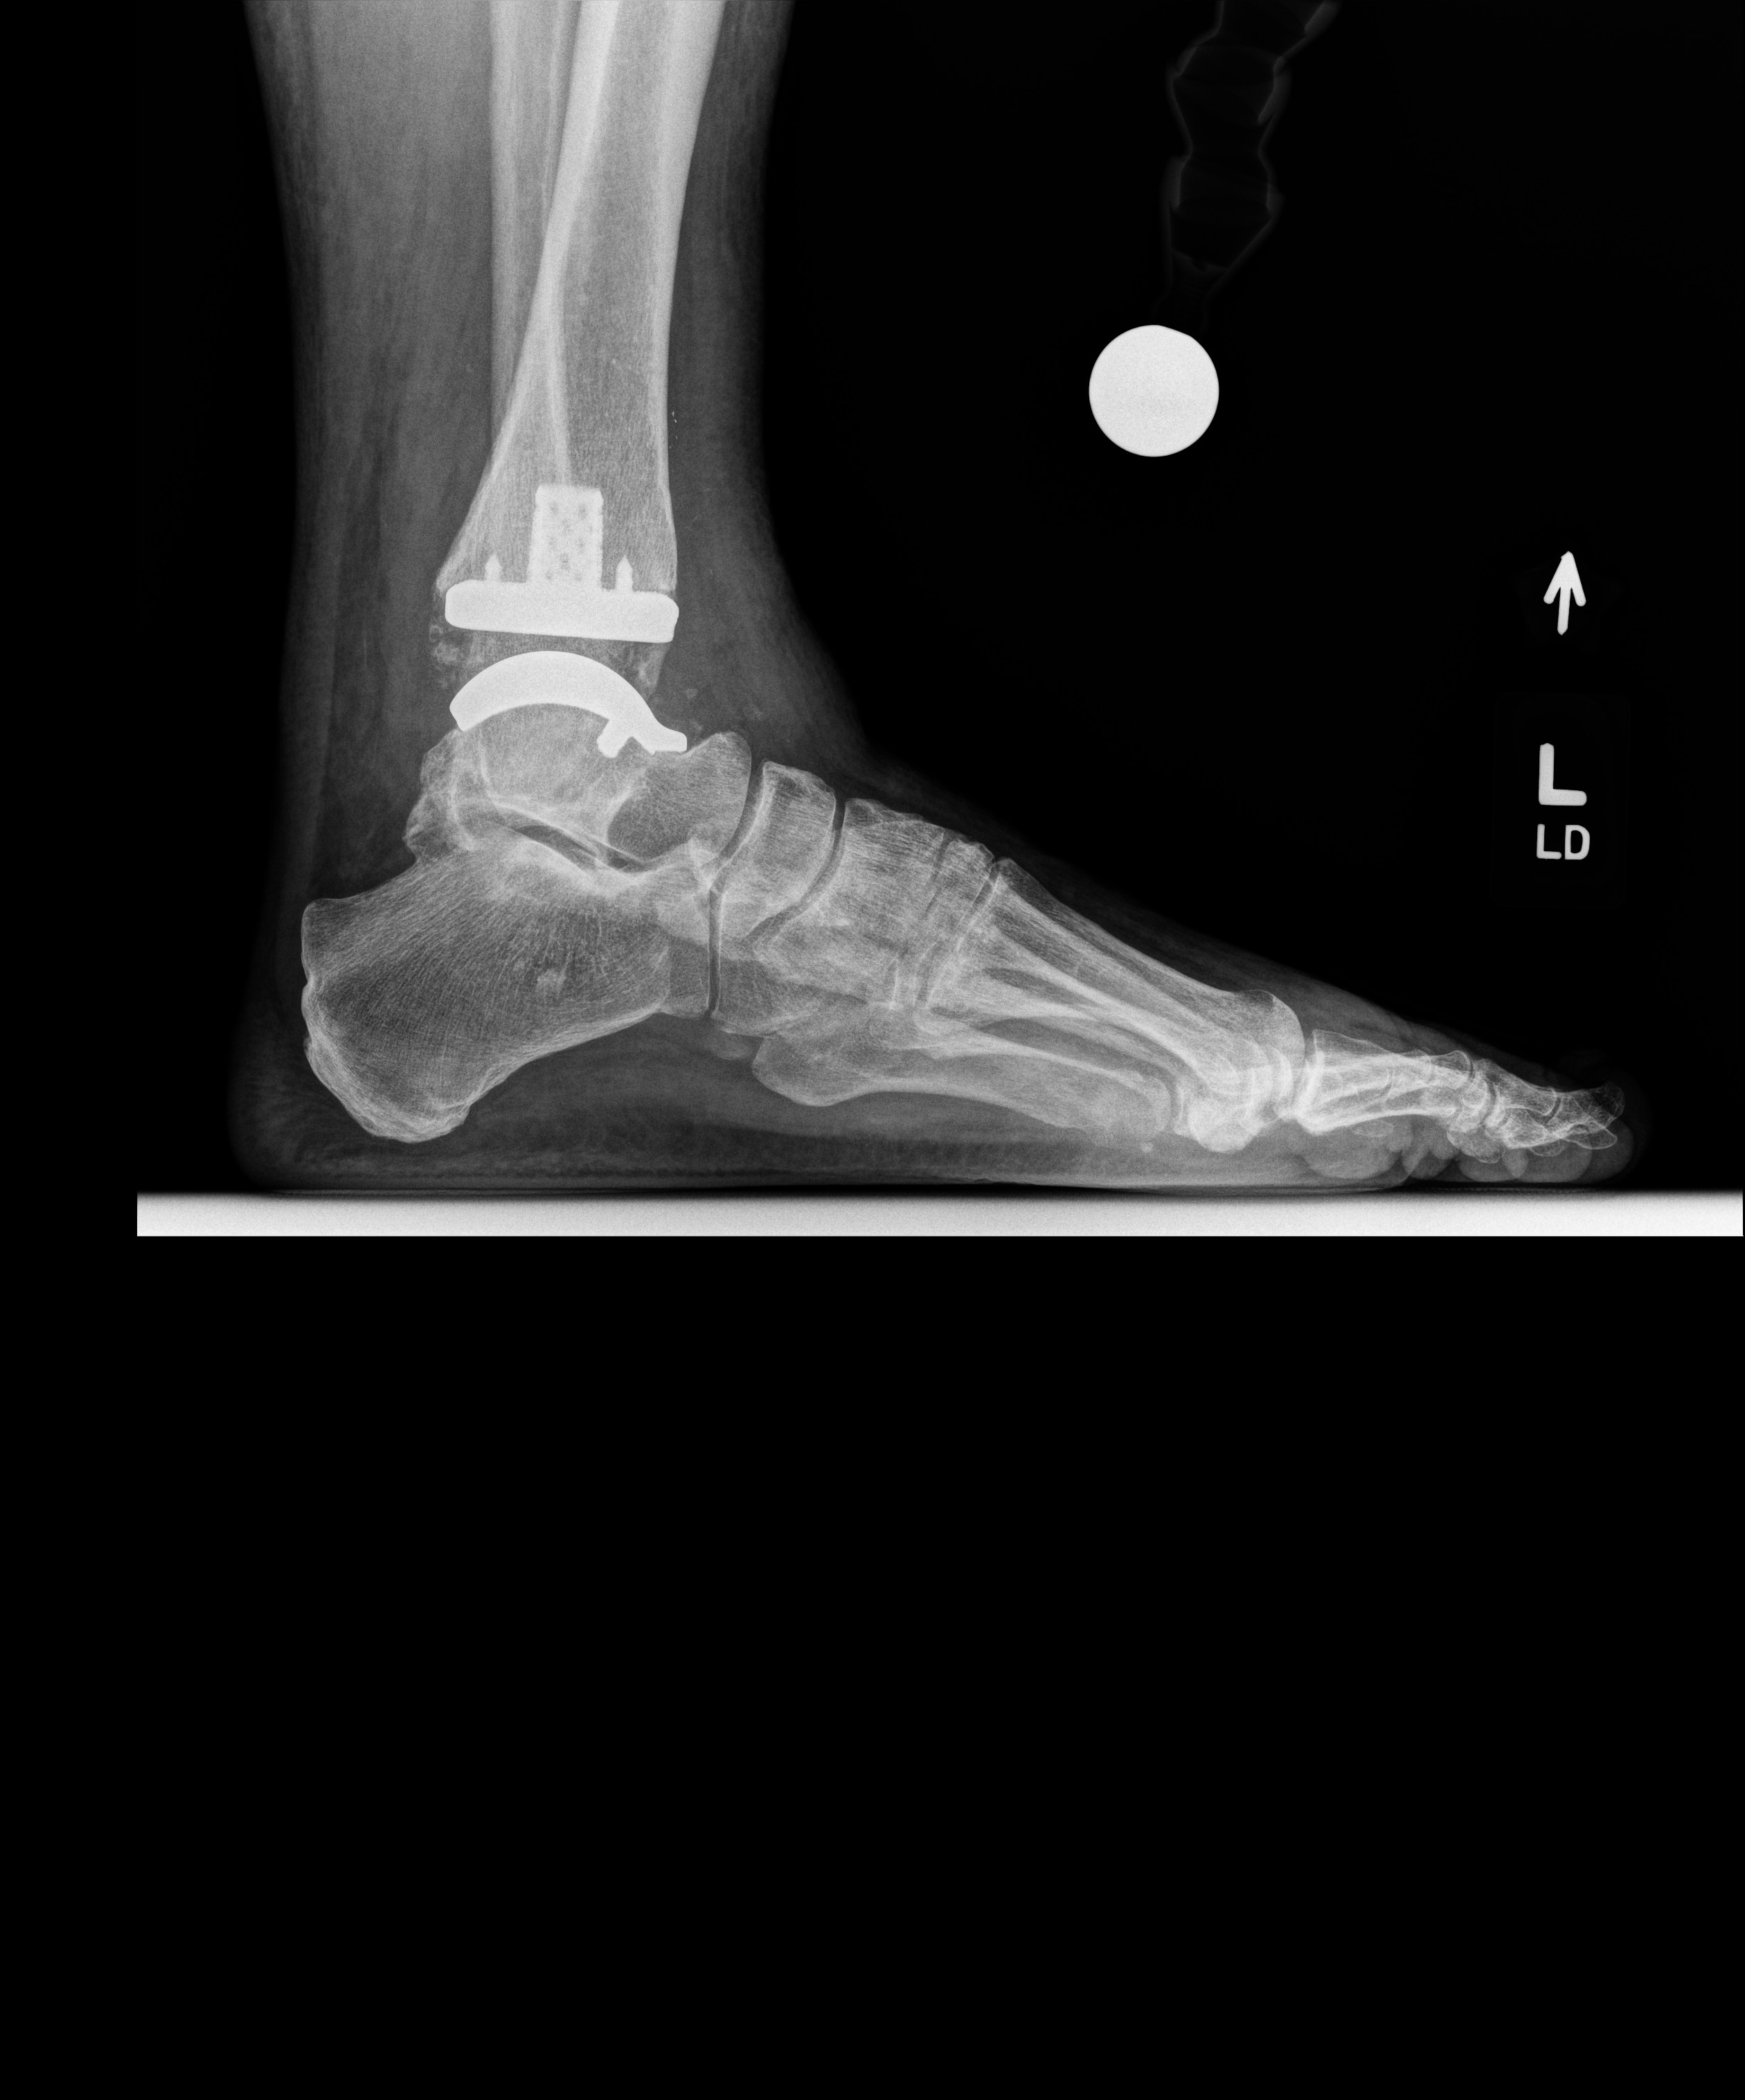

So I had mine done in March... not 100% happy but so much better. Problem is I let mine go for too long (maybe you too) I didn't have some muscles and I need them to walk correctly. Best part is most of the major pain is gone...

This is what I got (video is my doctor): Exactech Vantage Total Ankle System

These were my latest xrays...

• image_10.jpg

image_10.jpg

1.4 MB · Views: 84